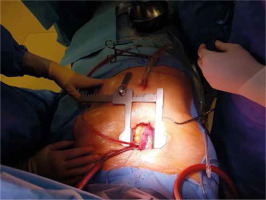

A skin incision is made over the handle of the sternum up to the 3rd or 4th intercostal space. The skin incision is usually about 5–6 cm. Its length depends on the structure of the chest and the length of the sternum. Subcutaneous tissue up to the fascia is dissected using cautery. At the level of the 3rd or 4th intercostal space on both sides, the fascia is completely dissected just above the upper edge of the sternal attachment of the rib. Then, arrow-shaped lines directed with the tip downwards are drawn from the notch of the zygomatic sternum to the designated two parasternal points. Then the breastbone is cut with an electric saw. In the next stage, thymic fat is dissected from the brachiocephalic vein. The pericardial sac is opened longitudinally and to the sides at the lower end as with a standard pericardial inverse “T” incision. On each side of the sternum, 3–4 pull-back pericardial sutures are placed, which are tied to the subcutaneous tissue in such a way that the pericardial sac covers the cut parts of the sternum. In the next stage, a site for cannulation and the aortic clamp is identified and prepared. The ascending aorta and the brachiocephalic trunk are mobilized (Figure 3).

Central cannulation is performed as the first choice. Heparin is administered at a dose of 3 mg/kg body weight intravenously titrated to the activated clotting time higher than 450 s. In the area of the brachiocephalic trunk, two Ti-Cron 2-0 purse - string sutures are applied. The aorta is cannulated using an EOPA cannula (Medtronic Inc, Minneapolis, MN, USA) and airlessly connected to the extracorporeal artery line. Venous outflow is provided by insertion of an MC2X two-stage cannula (Medtronic, Inc) into the right atrium. The cannula is then pulled out of the chest under the sternum through a small handrail under the xiphoid process, through which the chest tube is carried out after the surgery (Figure 4). At this stage, it is possible to start extracorporeal circulation. With the emptied heart, a 16 F vent (Medtronic Inc, Minneapolis, MN, USA) is inserted through the right superior pulmonary vein into the left atrium. The patient’s body temperature is maintained at 34°C.